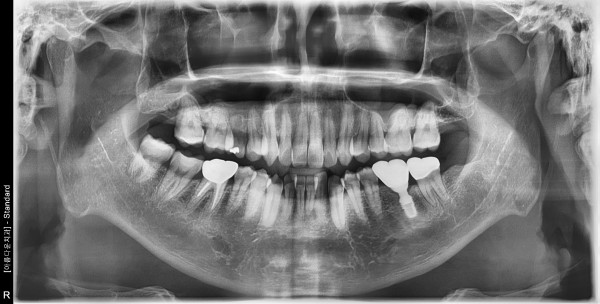

41세 남자 좌측구치부 임플란트식립